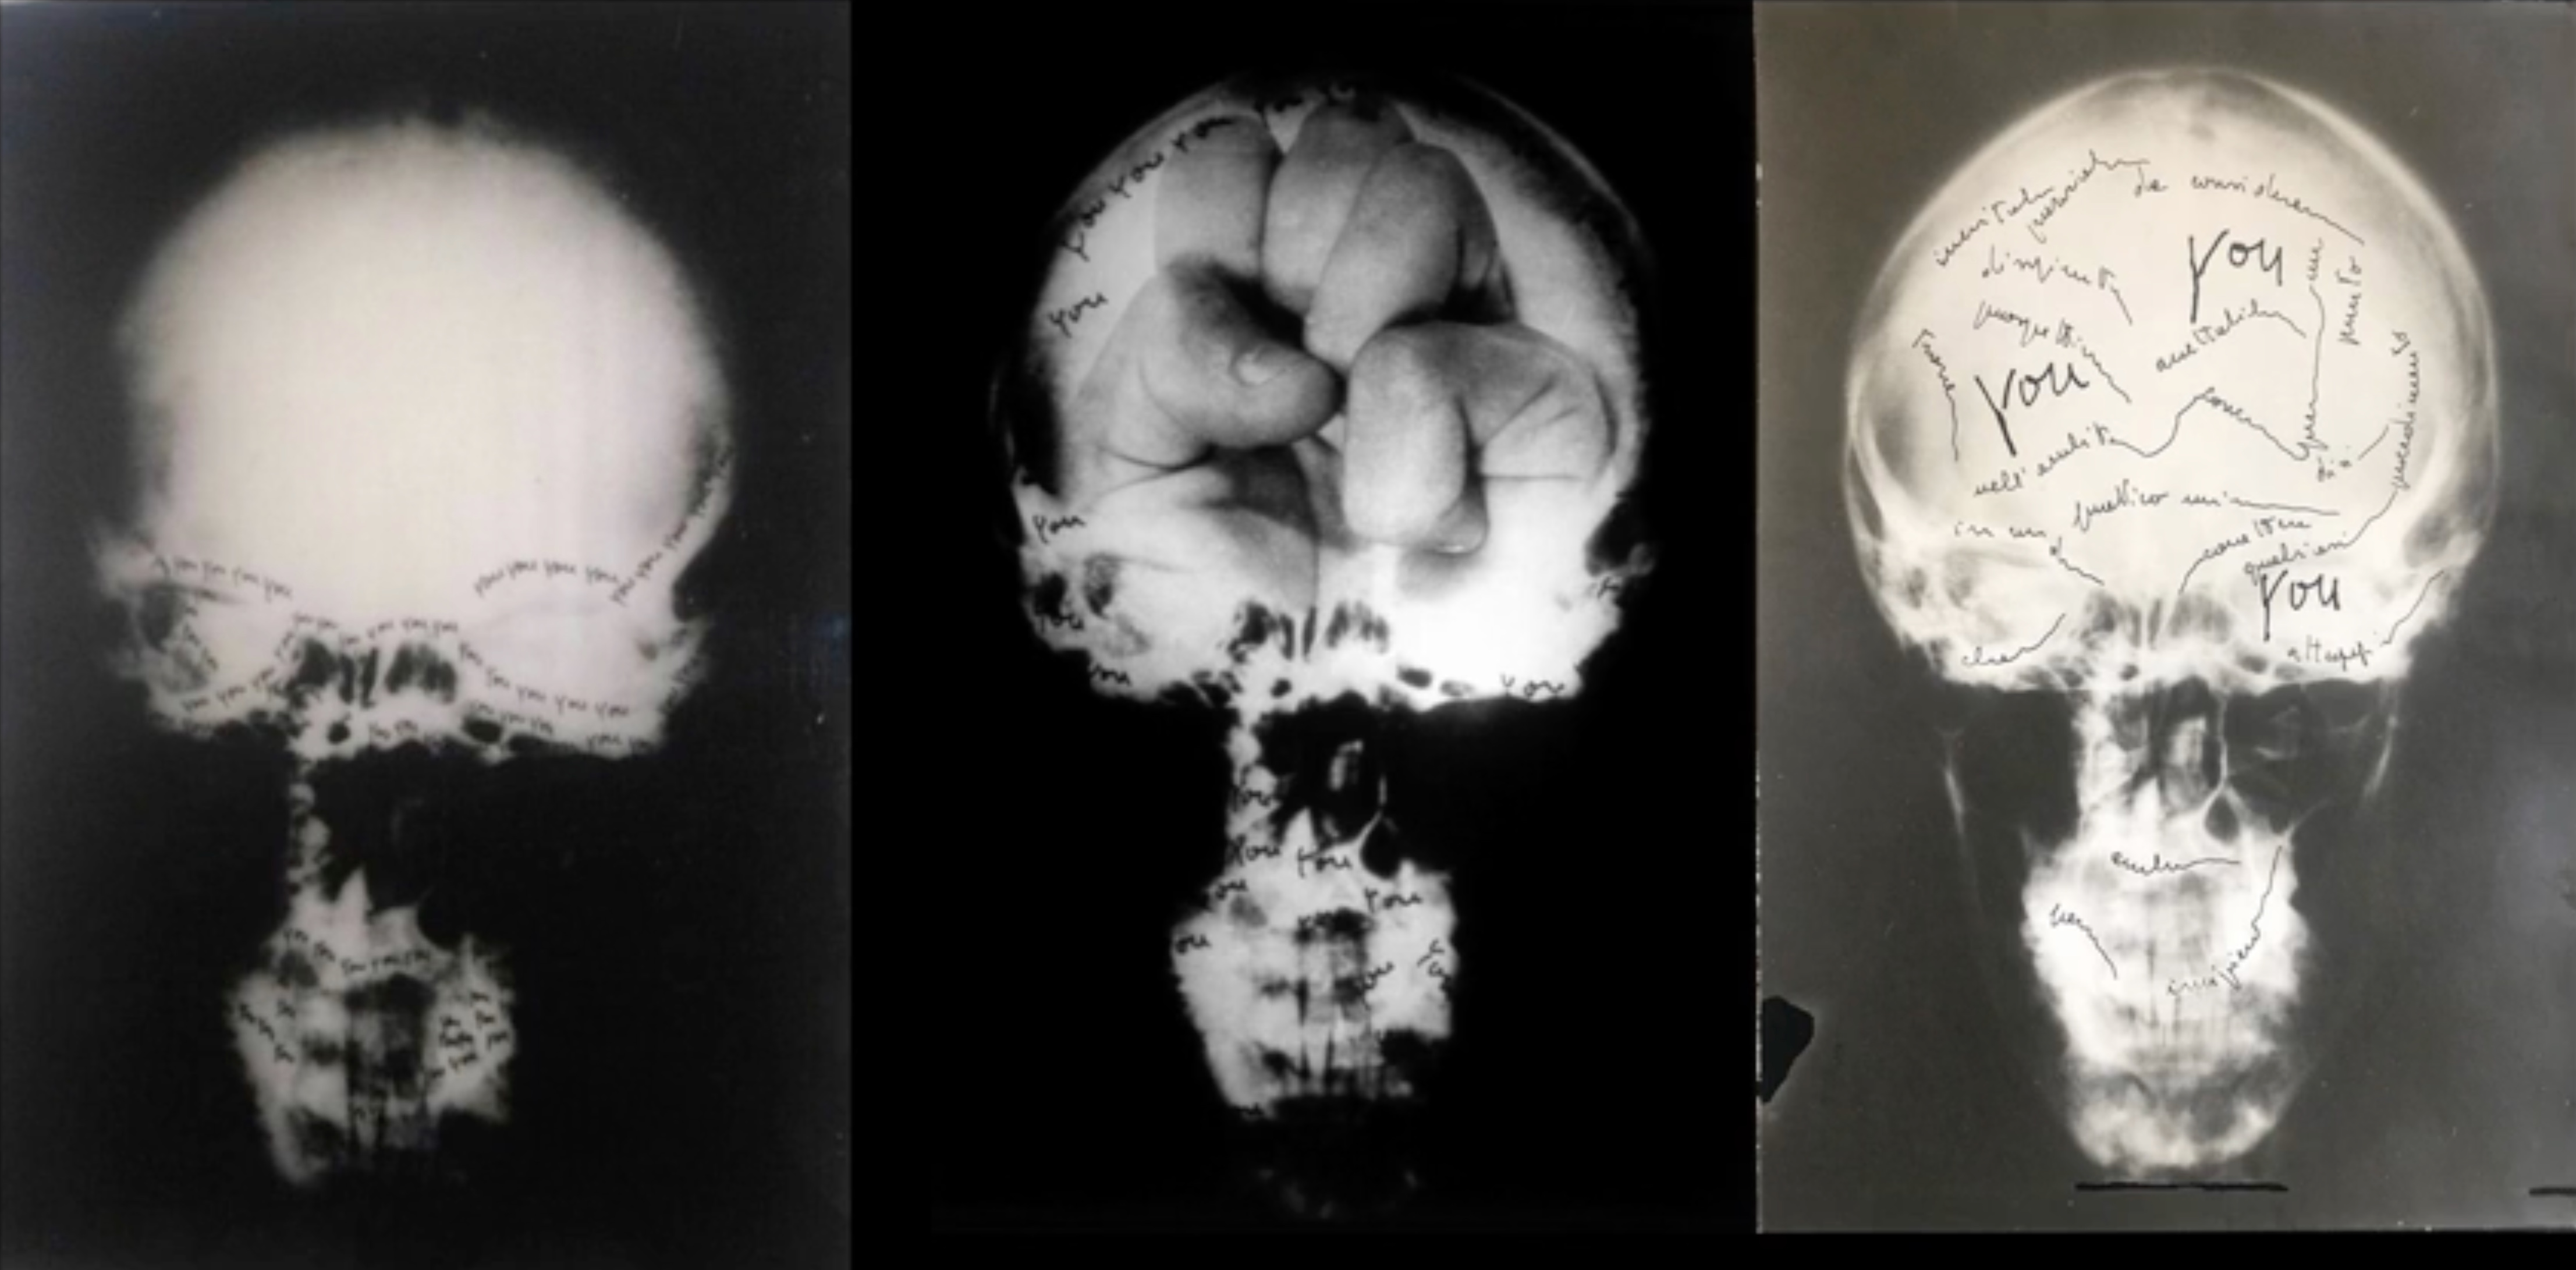

Ketty La Rocca, Craniologia, 1973, Courtesy Estate Ketty La Rocca & Kadel Willborn, Düsseldorf

Craniologia besteht aus Radiografien ihres Kopfes samt Halswirbelsäule aus unterschiedlichen Perspektiven, die sie mit Aufnahmen von Handhaltungen doppelbelichtet und zudem mit dem sich wiederholenden Wort “you” beschriftet auf Acrylglas übertrug. Als junge Frau hatte sie in der Radiologie gejobbt; nun arbeitete sie mit medizinischem Untersuchungsmaterial, aus dem Expert*innen auf eine Erkrankung schließen können, während die Bilddokumente für den Laien wenig von der gefährdeten Existenz transparent machen. Denn eine Röntgenaufnahme des Schädels macht Knochenstrukturen sichtbar, “sagt” aber wenig über sein Inneres aus. Malignes Gewebe von Weichteilen lässt sich eher in einem anderen, zu Beginn der 1970er Jahre entwickelten Bildgebungsverfahren, der Computertomografie (CT), erkennen. So entsteht einerseits der merkwürdige Eindruck, die verschiedenen Handmotive, mit denen Ketty La Rocca den Röntgenfilm überblendete, zeigten das Kopfinnere. Die Formationen der Hand – ein Handteller, ein einzelner ausgestreckter Finger, eine geballte Faust von der Handinnenfläche her gesehen, – sind es, die den Schädel anstelle der Hirnwindungen füllen würden. Andererseits erscheint die knöcherne Hirnschale als Projektionsfläche, als der Ort für Vorstellungen, für Bilder im weiteren Sinn, vielleicht auch für „Bilder“ einer Krankheit. Anders als das Gehirn sind Hände äußerlich, und Gestikulieren spricht eine eigene Sprache (auch jenseits von Gebärdensprache, mit der die Künstlerin sich ebenfalls befasste).

Wie bloß lässt sich unter diesen Bedingungen “Ich” sagen, wie sich in der ersten Person Singular repräsentieren? Insofern galt das “you” in den 1960er und frühen 1970er Jahren möglicherweise allen Frauen, die versuchten, “das Bild sich selbst gegenüber zu rehabilitieren”3 : Ich bin auch du. Im visuellen Klischee der Frau ist sich die Künstlerin “ein Muster der Entfremdung”4 , wie sie schrieb. Und ist sie sich nicht ebenso ein “Muster der Entfremdung” im Blick auf das Negativ ihres Hauptes, das von ihr und ihrer Krankheit abstrahiert? Denn auch der Kurzschluss eines radiografierten Schädels mit einem Totenkopf, dem ikonischen Zeichen für die Endlichkeit des Lebens schlechthin, bedient ein Klischee. Die galoppierenden Lettern you, you, you … markieren hier einzelne Schädelstellen samt Halswirbelsäule, und das Du-Echo gibt der Szene eine irritierende Konkretion. Bedenkt man ein Subjekt, das sowohl mit den physischen Symptomen, als auch mit der Imagination und den psychischen Folgen seiner lebensbedrohlichen Erkrankung lebt, erscheint das aufgetragene you wie eine Öffnung einer geschlossen gedachten Körperoberfläche, werden die einzelnen Buchstaben zu Poren. Simuliert der you-Schriftzug beispielsweise die Kontur der Augenhöhlen auf dem hellen Schädelrund, so betont er die Kontaktorgane, die Augen, die nach außen blicken, ebenso aber für eine Innenschau stehen können. Solche Durchlässigkeit liegt nicht im Abgebildeten, der gleichsam versiegelten Schädeldecke und der Hand-als-Gehirn, sie deutet in Richtung des anderen.

“Unter die Haut geht” nun die mehrteilige Serie Craniologia, Ketty La Roccas einzige künstlerische Arbeit, die nicht nur mit einer Ansicht operiert. Überblendet mit einer Handhaltung, wird das unter Haut und Haar Liegende, der Schädel und einige Wirbel, als weißer Schattenriss sichtbar. Damit bleibt die Künstlerin bei einer visuellen Oberfläche, die sich nach außen richtet, bei dem Bild, das sich an jemanden wendet, der es betrachtet, weil sie oder er von ihr “angesprochen” wird. Schließlich ruft jeder bloße Schädel die Assoziation des Totenkopfs hervor. Aber auch diesem Bild schien Ketty La Rocca zu misstrauen, seinen Symbolwert als Klischee von Vergänglichkeit zu hinterfragen. Hier ist dieses Hinschauen nicht das diagnostische eines Mediziners, die Bildserie richtet sich als künstlerische Artikulation eines Ichs an uns Kunstbetrachter*innen. Ich und Du sind nicht kategorial geschieden, folgen wir Ketty La Roccas Worten: “‘you‘ bedeutet auch ich”5 .

In Craniologia stehen Hand oder Finger sichtlich im Vordergrund, so wie sie aus der Halswirbelsäule herauszuwachsen und auf dem Schädelknochen aufzuliegen scheinen. Die Krankheit lässt sich nicht ertasten, der Tumor sich nicht berühren. Also bleiben die Handgesten ohne einen Gegenstand, eingekapselt wie die Geschwulst im Kopf. In der Doppelbelichtung mit dem Schädel entsteht jedoch visuell ein Hirn-Hand-Interface, und diese metaphorische Überschneidung von Denken und Fühlen wird zusammen mit dem you – Wort für Wort handgeschrieben, wie schon wiederholt betont – zu etwas, das das Individuum sowohl mit sich als auch mit der und dem anderen verbindet. Unter dem Vorzeichen des “-logos” in Kraniologie, diesem Komplott zwischen Visualität und Begriff, beschriftete Ketty la Rocca ihr individuelles Schicksal, ihre Erkrankung, mit den Zeichen einer Durchlässigkeit für das you, das Du. Wie auch könnte sie sich ihrer selbst in dieser Lebenssituation sicher sein? In Kontext der Frage nach der Subjektivität im unheilbar Kranksein lese und interpretiere ich das Anschreiben und Ansprechen eines Du als ein Bezugnehmen auf einen Körper, dessen Körper-Sein über den singulären Körper hinaus- und vom Geteilten von Körpern ausgeht.